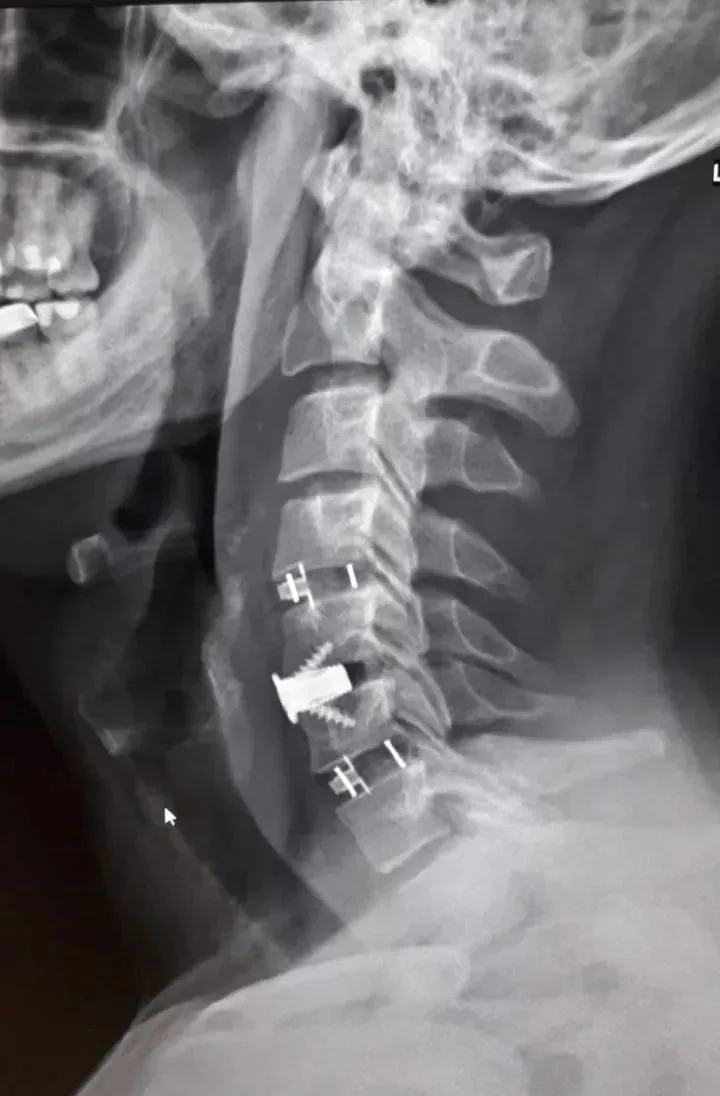

Мужчина долгое время страдал от остеохондроза шейного отдела. В августе прошлого года на фоне нагрузки боль усилилась, распространилась на правую руку, появились слабость и онемение. Консервативное лечение не помогало, и пациент поступил в БСМП №1 на плановую операцию. Диагноз: диско-остеофитный стеноз позвоночного канала на нескольких уровнях шейного отдела. Бригада под руководством заведующего нейрохирургическим отделением Павла Юрова провела уникальное комбинированное вмешательство – устранила сдавливание и стабилизировала позвоночник с помощью титановых конструкций. Уже через три часа после операции пациент встал на ноги. Боли ушли, мышцы вернули силу, онемение почти исчезло. На пятые сутки мужчину выписали на реабилитацию. Врачи отметили, что ранняя активизация пациента стала важным фактором успешного восстановления.

Мужчина долгое время страдал от остеохондроза шейного отдела. В августе прошлого года на фоне нагрузки боль усилилась, распространилась на правую руку, появились слабость и онемение. Консервативное лечение не помогало, и пациент поступил в БСМП №1 на плановую операцию.

Диагноз: диско-остеофитный стеноз позвоночного канала на нескольких уровнях шейного отдела. Бригада под руководством заведующего нейрохирургическим отделением Павла Юрова провела уникальное комбинированное вмешательство – устранила сдавливание и стабилизировала позвоночник с помощью титановых конструкций.

Уже через три часа после операции пациент встал на ноги. Боли ушли, мышцы вернули силу, онемение почти исчезло. На пятые сутки мужчину выписали на реабилитацию. Врачи отметили, что ранняя активизация пациента стала важным фактором успешного восстановления.